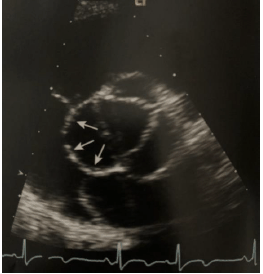

De acordo com a imagem ecocardiográfica abaixo obtida de um paciente jovem assintomático, em avaliação cardiológica de rotina, analise as afirmativas abaixo.

I. Os aneurismas congênitos do seio de Valsalva possuem formas regulares, com seios de paredes finas e invaginadas

II. A ruptura do aneurisma do seio coronário direito ocorre dentro do VD, a do seio coronário esquerdo ocorre dentro do AE e a do seio não coronário ocorre dentro do AD

III. Os aneurismas do seio coronário adquiridos são geralmente decorrentes de traumas torácicos e apresentam formato mais arredondado

IV. O fluxo na fistula da aorta tem seus componentes sistólico e diastólico bem marcados, refletindo a diferença das pressões entre a aorta e a câmara que recebe o fluxo

Estão corretas as afirmativas: